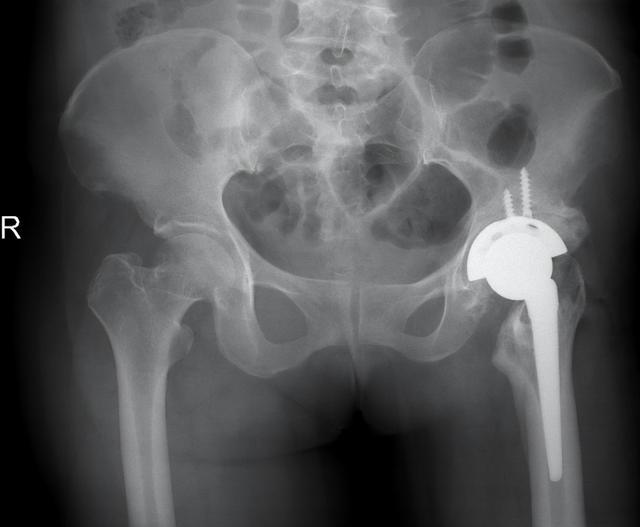

▲患者术前术后影像资料

蒋女士还合并有高血压、糖尿病等多种基础疾病,血压最高达186/92mmHg。经多学科联合诊治,患者血压、血糖等调至正常范围。湖南省脑科医院(湖南省第二人民医院)骨关节科主任李宝军博士率领手术团队为患者制定了周密的手术方案,并成功实施髋关节置换手术。患者术后第一日即能下地行走,髋关节屈伸、旋转活动明显改善,患者及家属对治疗效果非常满意。